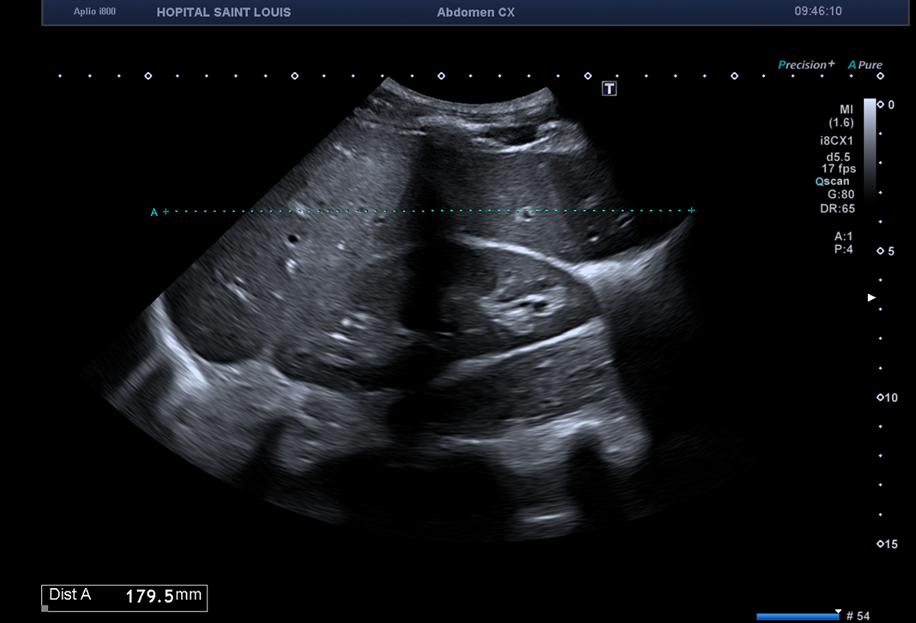

L’échographiste utilise une sonde convexe abdominale de basse fréquence pour réaliser l’examen et détecte un foie homogène, augmenté de taille, sans lésion focale.

Ici, la flèche hépatique est mesurée devant le rein droit, elle aurait pu être mesurée sur la ligne médio claviculaire droite.

Le morphotype du patient (longiligne, bréviligne…) doit être pris en considération avant de conclure à une hépatomégalie.

Cependant, sur cette image la profondeur et la focale sont mal réglées. En effet la profondeur doit être adaptée à l’organe étudié, et sur cette image, il y a trop de profondeur. La focale aurait pu aussi être ajustée, en la remontant.